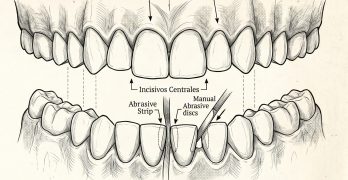

BDR CCCIX: Técnicas de reducción de esmalte en ortodoncia

Para cerrar nuestra semana y directo de nuestro infame Baúl del Recuerdo traemos una nota llamada Técnicas de reducción … [Leer más...] acerca de BDR CCCIX: Técnicas de reducción de esmalte en ortodoncia